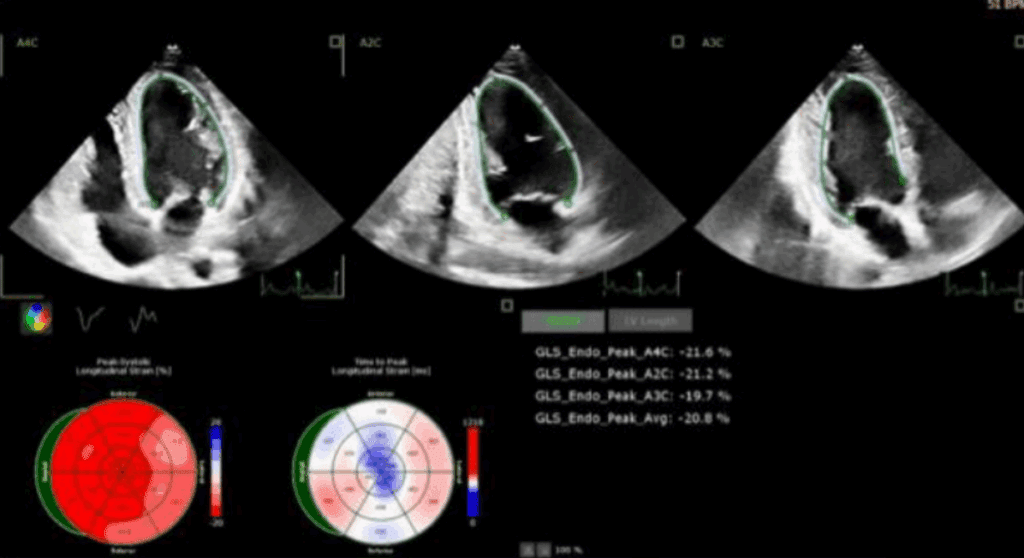

Odkształcenie mięśnia sercowego (strain) jest metodą szeroko wykorzystywaną w diagnostyce echokardiograficznej w grupie chorych z przerostem mięśnia lewej komory serca (ang. left ventricular – LV) o różnej etiologii. W tej grupie chorych standardowe przezklatkowe badanie echokardiograficzne (ang. transthoracic echocardiography – TTE) rozszerzone o pomiar odkształcenia lewej komory serca (ang. left ventricular strain – LV-GLS) ułatwia rozpoznanie, jak i pozwala na różnicowanie przyczyn przerostu LV.

W artykule przedstawiono przypadki kliniczne różnych pacjentów z chorobami układu sercowo-naczyniowego oraz przerostem mięśnia sercowego, u których pomiar odkształcenia (strain) LV istotnie ułatwia diagnostykę różnicową.